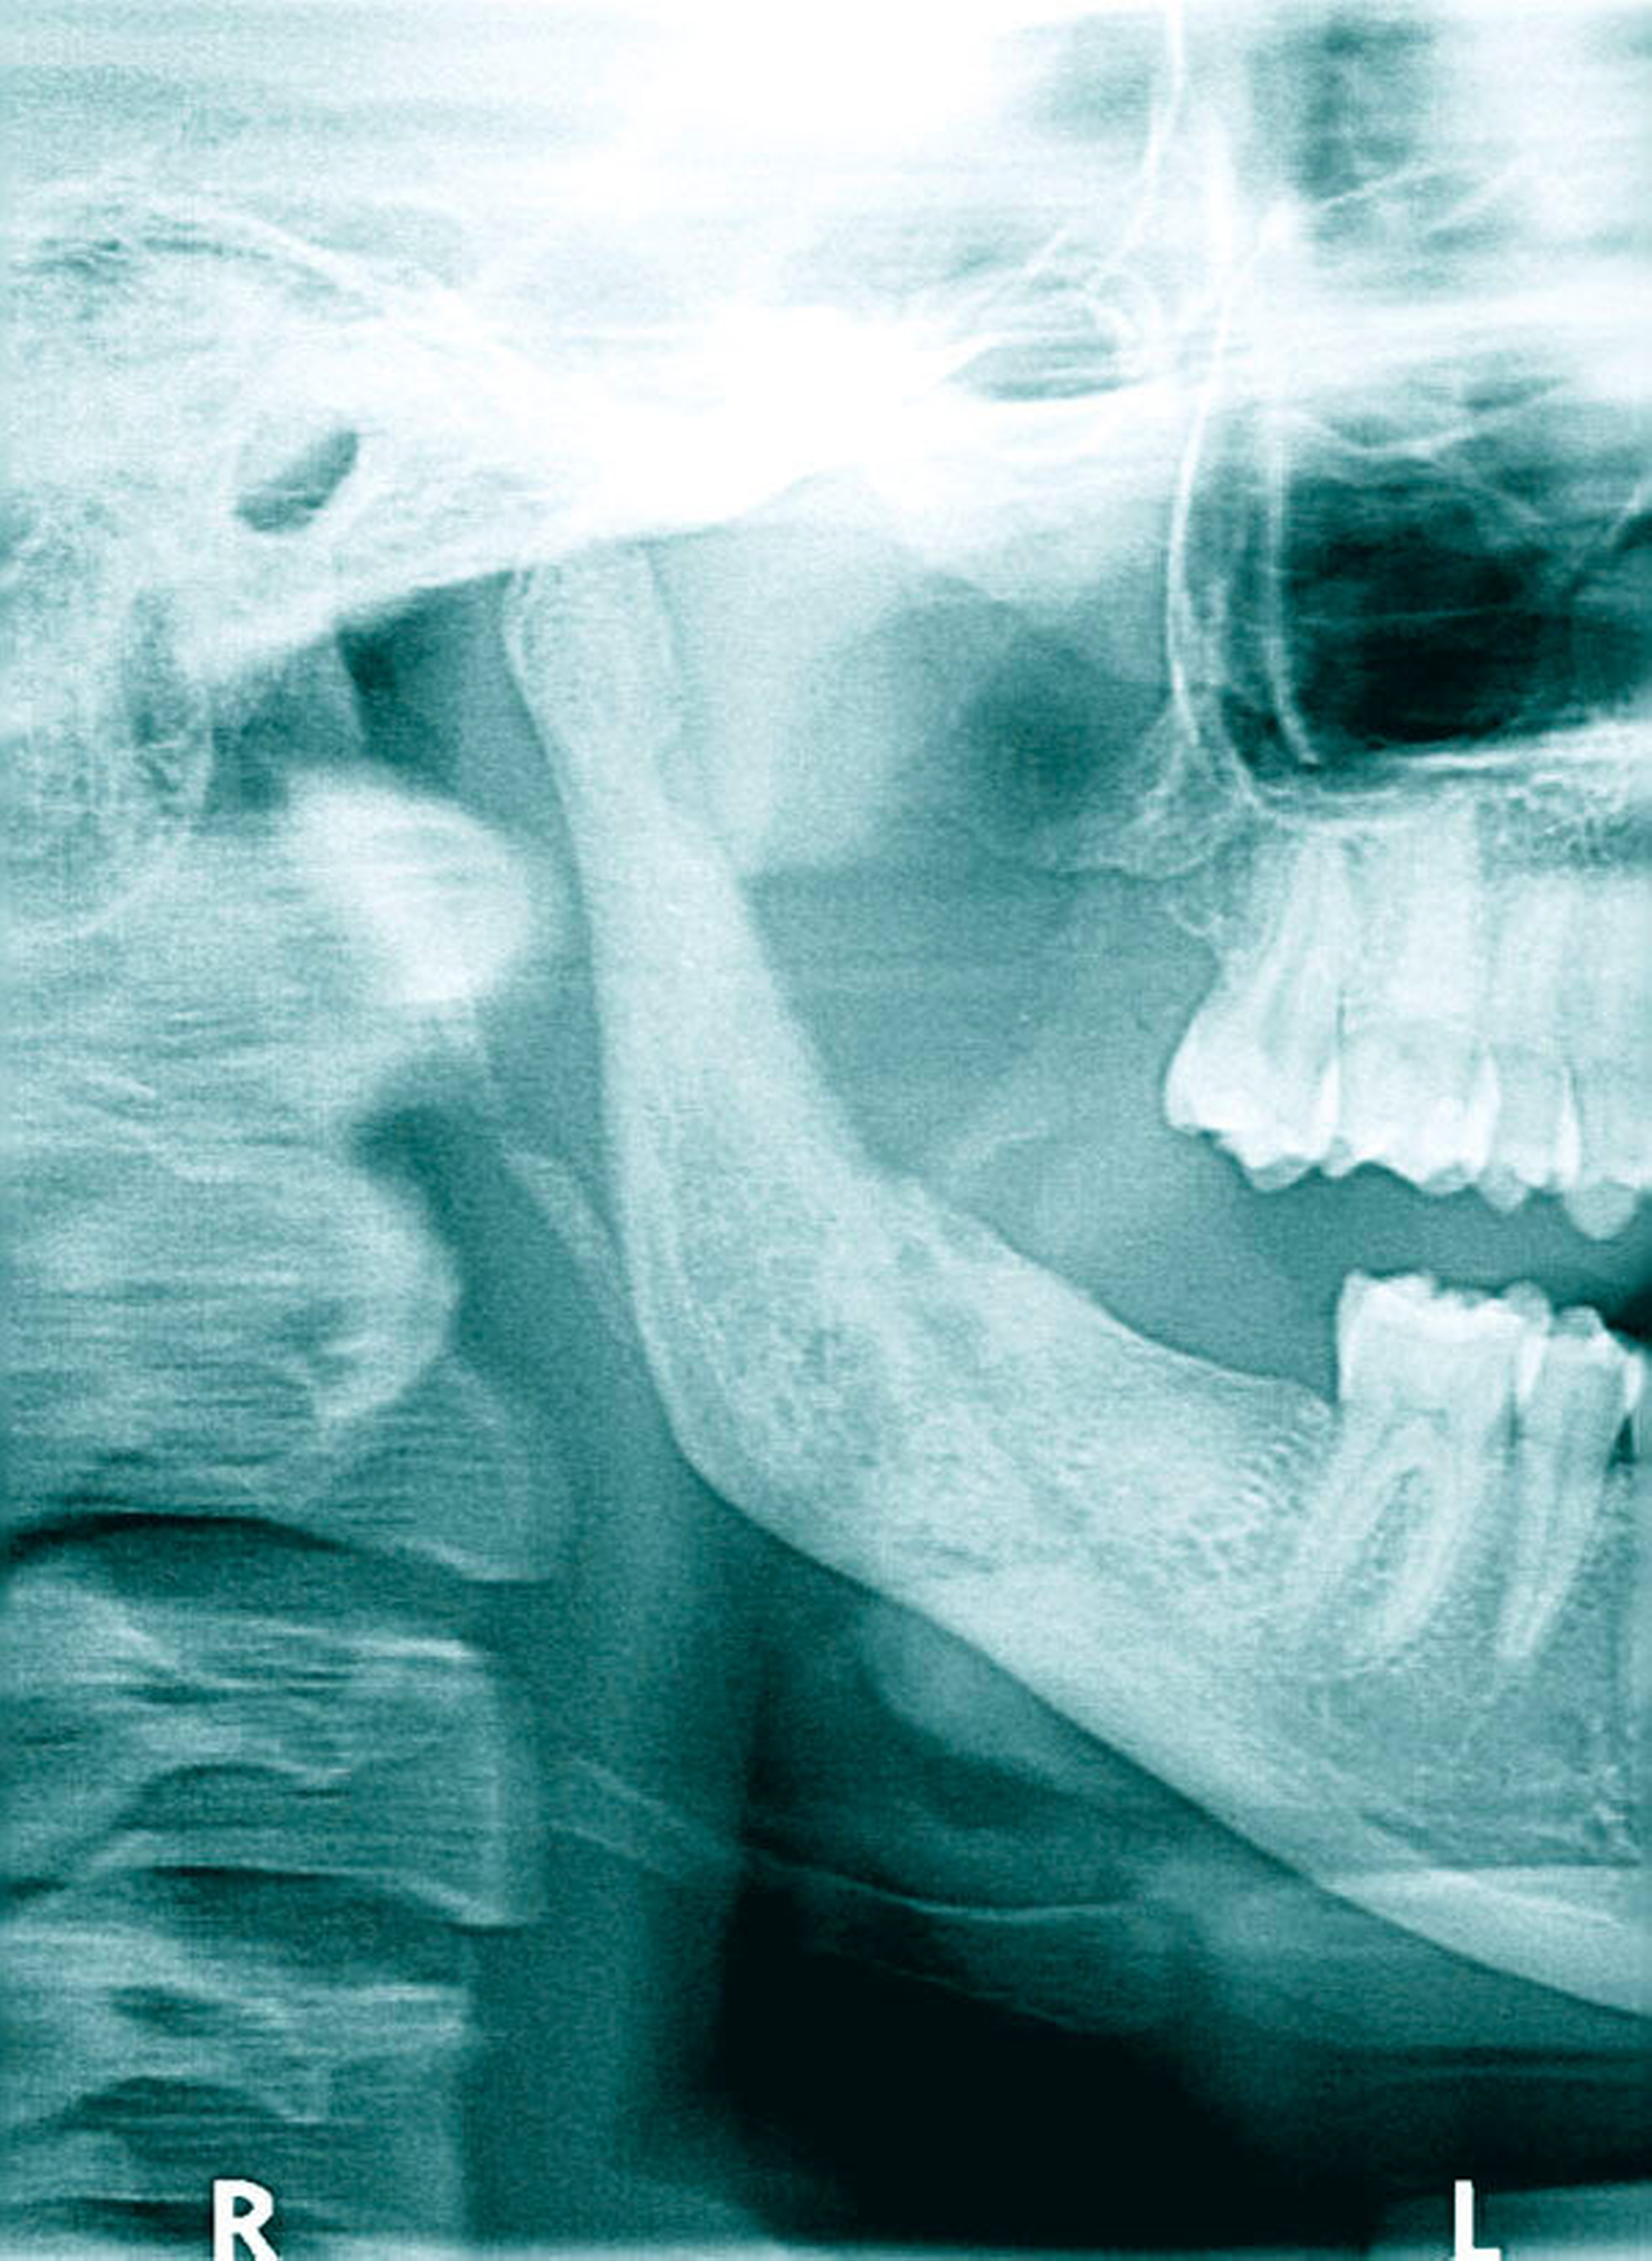

Innerhalb der nächsten acht Wochen, unter laufender oraler Antibiotikatherapie, kam es zunächst erneut zu einer Beschwerdebesserung. Als plötzlich wieder stärkere Schmerzen im Unterkiefer auf der rechten Seite auftraten, zeigte sich im erneuten OPG nun eine Osteomyelitis in regio 048 bis zum Processus muscularis (Abbildung 3). Hier wurde stationär, unter intravenöser Antibiose, die Dekortikation, die Entfernung des gelockerten und schmerzhaften Zahns 47, die Einlage von Gentamycinschwämmchen und plastische Deckung durchgeführt, sowie eine naso-gastrale Ernährungssonde appliziert. Auf eine Kontinuitätsresektion und Anlage einer Reko-Platte konnte zunächst verzichtet (Abbildung 4) werden.